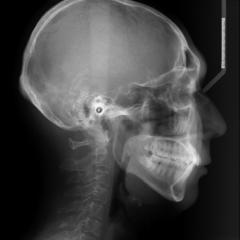

CTスキャンと矯正歯科治療

矯正治療への利用では、術前の検査で顎骨の状態を正確に把握できるため、歯の移動の限界が予測でき、さらに軟組織の状態もわかるので治療計画の立案に役立ちます。

最適な治療方法を導く事は、治療期間の短縮にもつながります。